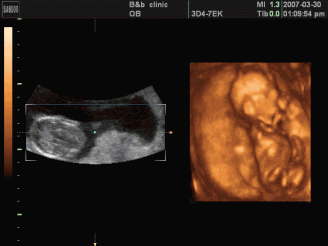

5D四维彩超排畸检查的准确度与设备有很大关系,睢宁东方医院斥巨资引进先进三星麦迪逊WS80A   5D四维彩超,其高清细腻的画面,逼真的立体成像,呈现出更真实、更详细的胎儿图像,提高临床诊断的准确性。

04